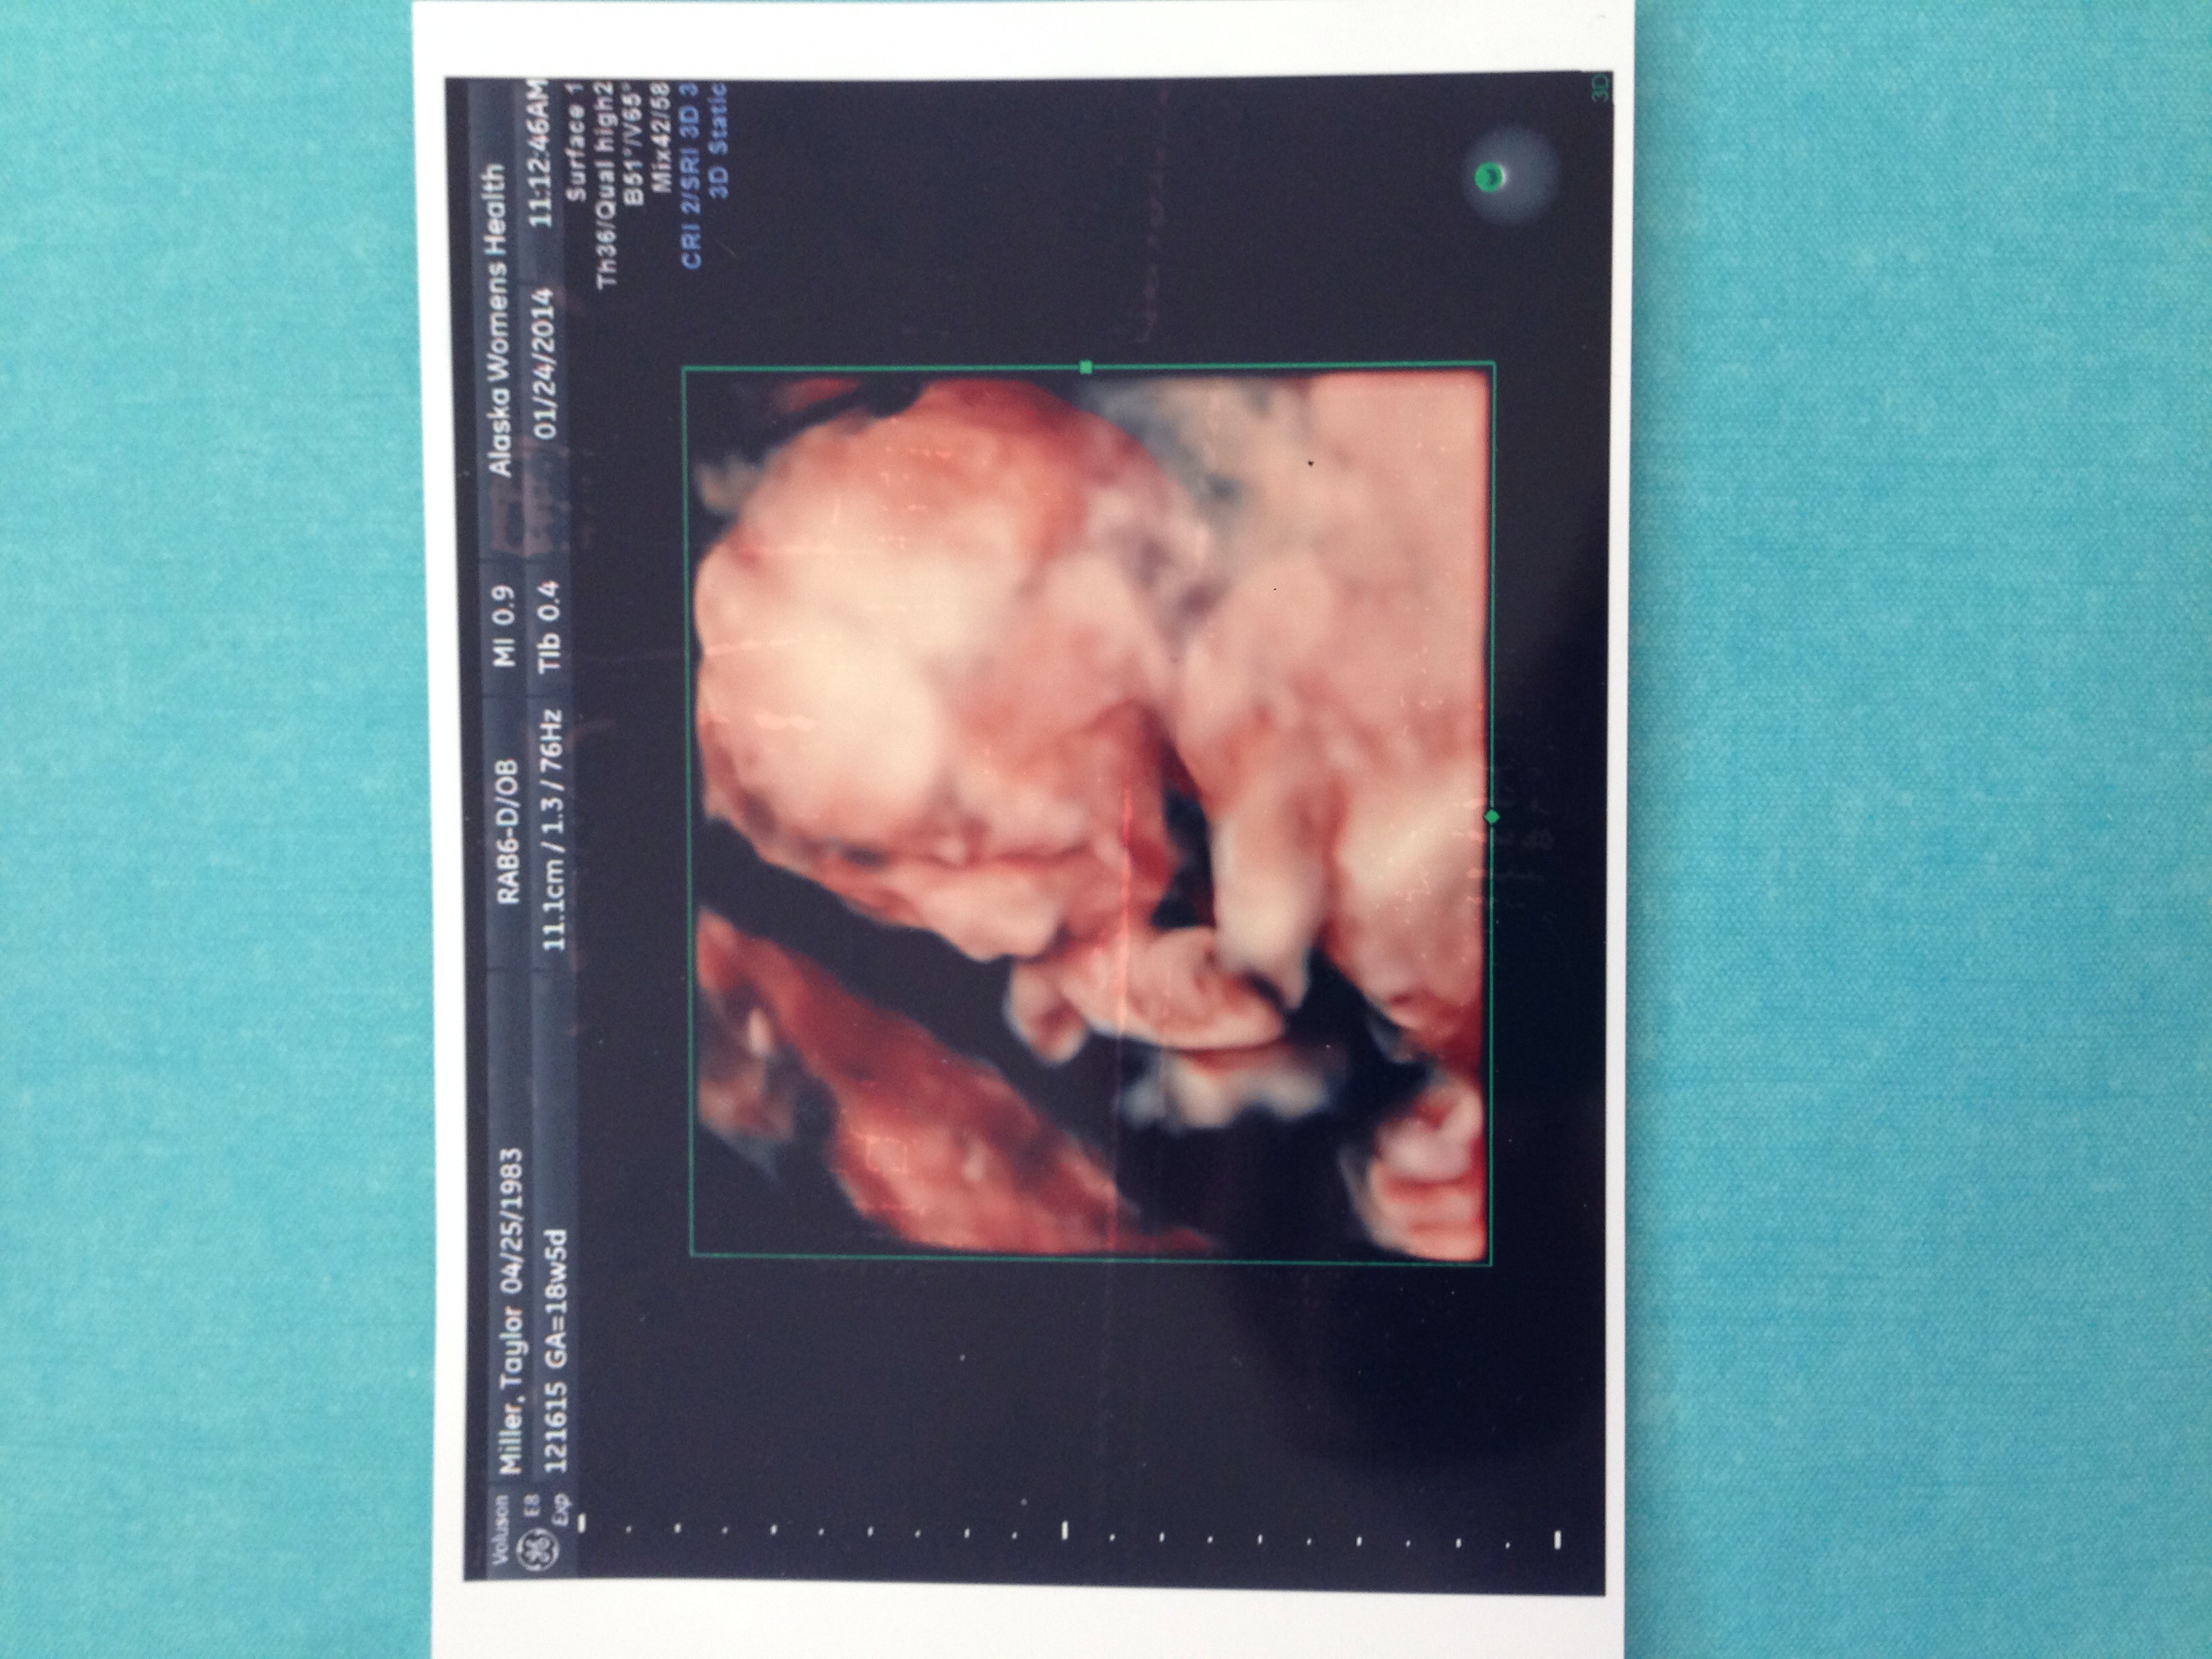

Feb 20/14 3D US - its a GIRL!!!!! @ 22w3d

But wow - the pictures you guys have in 3D and 4D are really amazing! If nothing else, the scientific aspect is really awesome. To think that when my grandmas were pregnant with my mom and dad, neither of them were even given ultrasounds at all. We've come a long way!